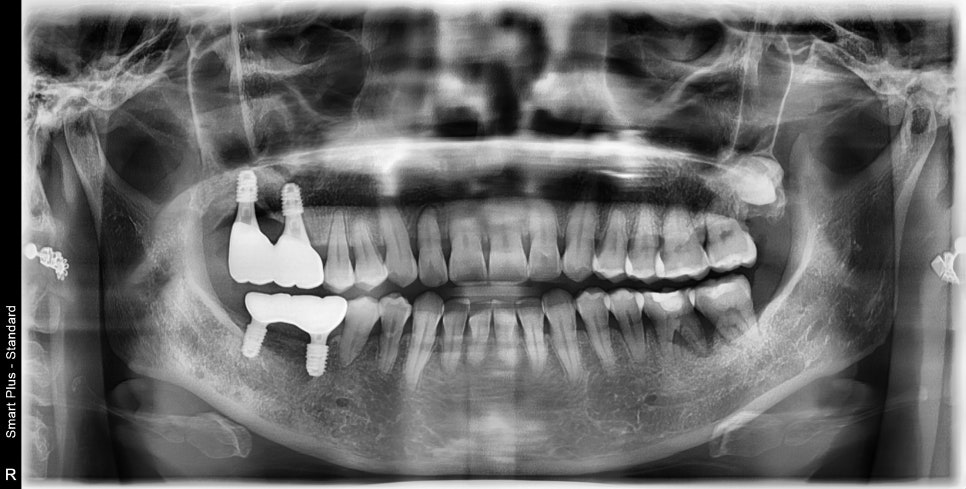

발치 후 3개월 정도의 시간이 지나서 주변골의 리모델링이 완료된 후의 사진입니다.

예상했던 대로 최후방 치아의 뿌리의 절반이 뼈로 덮여있어야 할 부분이 재생되지 않고 그대로 노출되어 있었습니다.

이런 경우 시간이 지날수록 노출된 뿌리의 시린 증상이 전과 똑같아질 것이고

임플란트의 유지적인 측면에서도 동시에 수술을 해서 고정력을 확보하는 것이 더 중요했습니다.

(표시된 선의 잔여골이 매우 부족하기 때문에 상악동 거상술이라는 뼈이식과 동시에 맨 끝 한 개의 임플란트만 수술을 한다면

임플란트 고정력이 상당히 낮아질 것입니다.)

상악동 거상술이라는 부족한 뼈의 볼륨의 증대시켜주는 수술과 동시에

임플란트 식립을 진행했습니다.

예상했던 것처럼 맨 끝부분은 골질이 매우 물렀기 때문에 수술 후에도 충분한 시간을 기다리기로 했습니다.

일반적으로 위턱뼈 같은 경우 3개월이면 임플란트의 고정력이 생기지만

이 케이스 같은 경우 발치 후 골질이 매우 물렀기 때문에 6개월 이상의 시간이 소요되었습니다.

잘 도와주시고 기다려주신 덕분에 처음 예측했던 골 형성과 골이식재도 잘 유지가 되고 있었습니다.